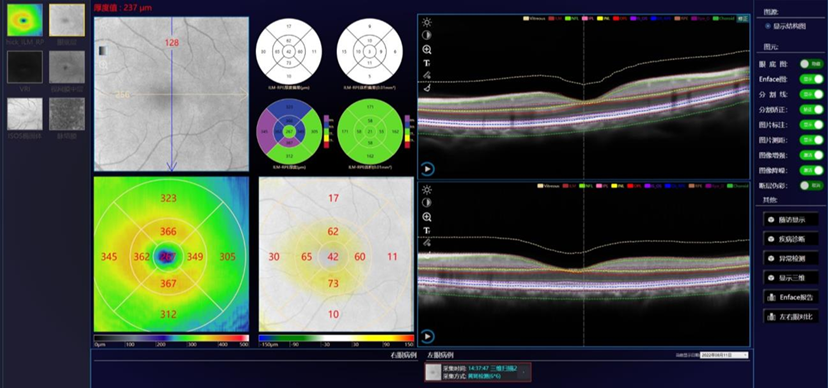

Análisis Macular 3D

• Análisis de grosor de punto único

• Análisis de grosor central

• Análisis volumétrico

• Análisis de grosor promedio

• Escaneo macular 3D de 6mm x 6mm y de 9mm x 9mm

Examen con escaneo en modo: 12mm x 6mm

Escaneo único para obtener simultáneamente datos de la mácula y del disco óptico del paciente